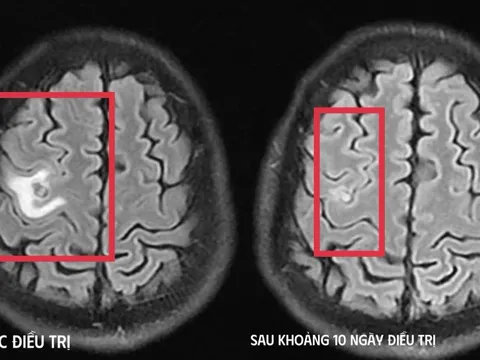

Lô thuốc viên nén Tegrucil-1, hoạt chất Acenocoumarol hàm lượng 1mg của Công ty CPDP Đạt Vi Phú không đạt chất lượng mức độ 3 theo quy định của pháp luật về dược (Ảnh minh họa).